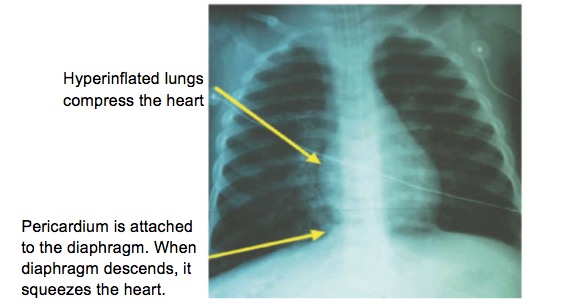

2- Severe air trapping in the lower airways causes hyperinflation. With each inspiratory effort, the heart is squeezed by the overinflated lungs and by the pericardium. The pericardial compression develops because the pericardium attaches to the diaphragm, and the diaphragm is flattened in patients with severe asthma. Each time the patient breathes in, the diaphragm moves downward. This adds additional tension to the pericardium and impedes filling of the heart. Thus stroke volume is decreased during inspiration, resulting in pulsus paradoxus. See the Figure.

Figure 1. Chest x-ray of a child with asthma illustrates the relationship between the lungs and heart. As the lung volume increases, the heart is compressed. In addition, the parietal pericardium is attached to the diaphragm. As the child inhales, the diaphragm flattens further and pulls the pericardium more tightly around the heart. Both of these actions impede venous return and thus impair stroke volume during inspiration, leading to the pulsus paradoxus.